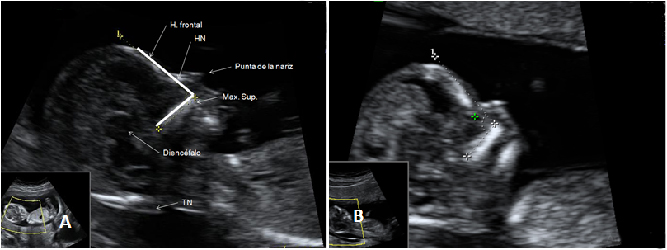

La ecografía en 4D (vídeo) no deja lugar a dudas. Se trata de un embarazo de siameses de 11 semanas de gestación, que están unidos por la zona abdominal, ya que comparten una pequeña parte de hígado. La movilidad de los bebés es reducida, como vemos en las imágenes, debido a la unión de sus cuerpos. Uno de los hermanos (el de la derecha) mueve la cabeza hacia atrás, mientras las piernas se entrecruzan. Los especialistas siguen este tipo gestaciones muy de cerca y valoran la separación quirúrgica de los bebés, una vez que se produce el parto.